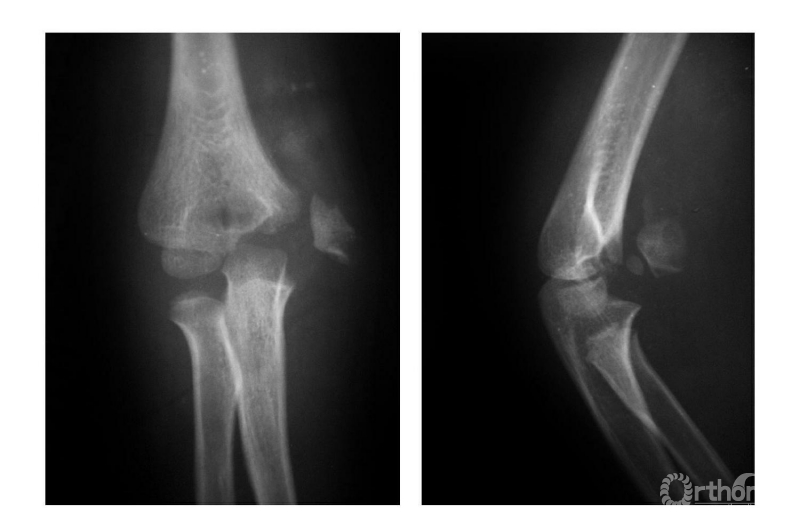

一、骨骺显露前期

例:6岁男孩右肘伤后(图1),内上髁损伤后肿胀,局部可触到活动的骨块,但X线片未见异常(因该骨骺尚未骨化)。5年后拍片健侧(左侧)内上髁骨骺正常显现,右侧内上髁骨骺呈一三角形骨片并略下移(图2)。

图1

图2